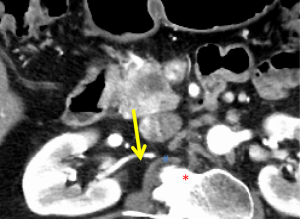

The first and most critical step in the management of PC is the determination of the clinical stage of disease and establishment of a histologic diagnosis. All disease-specific and stage-specific treatment planning is predicated on this step. With PC, it is critically important to use standardized, objective radiologic criteria for clinical staging. Modern imaging techniques have revolutionized the clinical staging of PC. Before the development of multidetector CT, up to 30% of patients with presumed resectable PC were found, at the time of operation, to have either metastatic disease or local tumor-associated vascular invasion which precluded resection (28). Currently, precise and objective anatomic radiographic criteria are used to determine the extent of the tumor-vascular relationship and to categorize clinical staging (Table 3). PC can be broadly divided into patients with inoperable disease (metastatic or locally advanced) and operable disease [borderline resectable (BLR) or resectable]. The majority of patients will present with metastatic disease, as evidenced by ascites/peritoneal implants, liver, or lung metastases. In the absence of metastatic disease, the clinical stage is determined by the relationship of the primary tumor to adjacent vasculature. As a general rule, any tumor abutment (≤180 degree tumor-vessel interface) or encasement (>180 degree) of the celiac axis, common hepatic artery, or SMA should be considered a contraindication to immediate surgery. A patient is deemed to have locally advanced, unresectable disease when: (I) the tumor encases the SMA or celiac axis, as defined by >180 degrees of the circumference of the vessel; or (II) there is occlusion of the SMPV confluence without the possibility for venous reconstruction (Figure 1). Patients who have tumor abutment, without encasement, of the SMA or celiac axis, or short segment encasement of the hepatic artery are considered to have BLR PC (Figure 2) (29). In addition, patients with tumors that cause >50% narrowing or short segment occlusion of the SMV/PV that may be amenable to reconstruction are also considered to be BLR. There is emerging consensus that even more subtle tumor-vein abutment may be best considered BLR, especially with respect to the use of neoadjuvant therapy rather than surgery-first (30). Finally, patients who have radiographic lesions which are indeterminate for metastases (usually too small to accurately characterize), even in the absence of SMA abutment or venous narrowing, are also considered by some institutions to have BLR PC (31). Radiographic findings of a resectable PC are (I) the absence of tumor-arterial abutment or encasement; and (II) <50% narrowing of the SMV/PV (Figure 3).